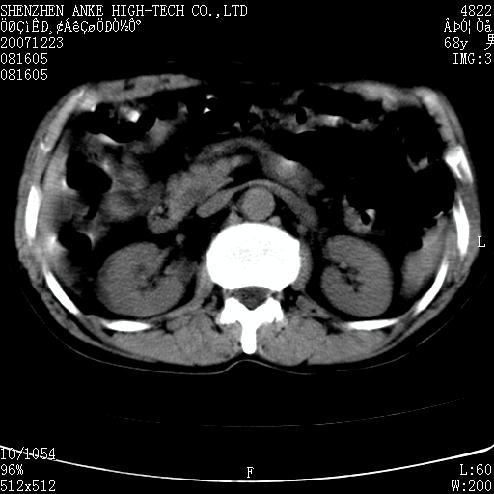

患者:男,63岁,2年前胆囊切除术后,现右上腹部剧烈疼痛近2天.

有无外伤史?右肾包膜下血肿可疑。

主要是问右肾有没有问题?患者无明显外伤史.

未见异常,病人差闭气,伪影较多.

肠道准备不好,干扰影大。

肠道气体伪影干扰太大了,应该是干扰所致,未见明显异常。

肠道准备不好,胃底后壁显示不清,右肾改变考虑为伪影。

上腹部ct平扫未见明显异常。(肠道气体较多,患者呼吸了)